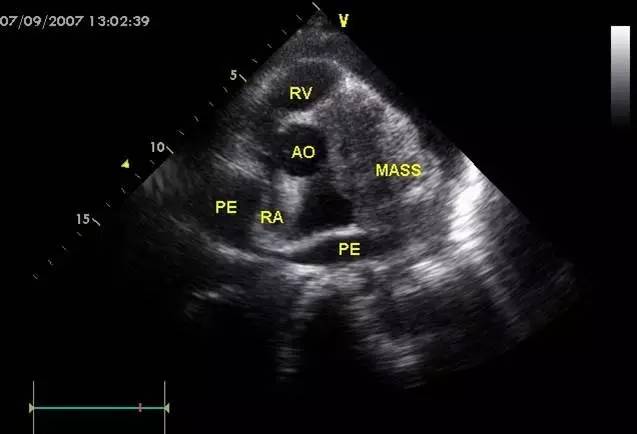

l超声心动图是一线检查

cardiac tamponade and pulsus paradoxus